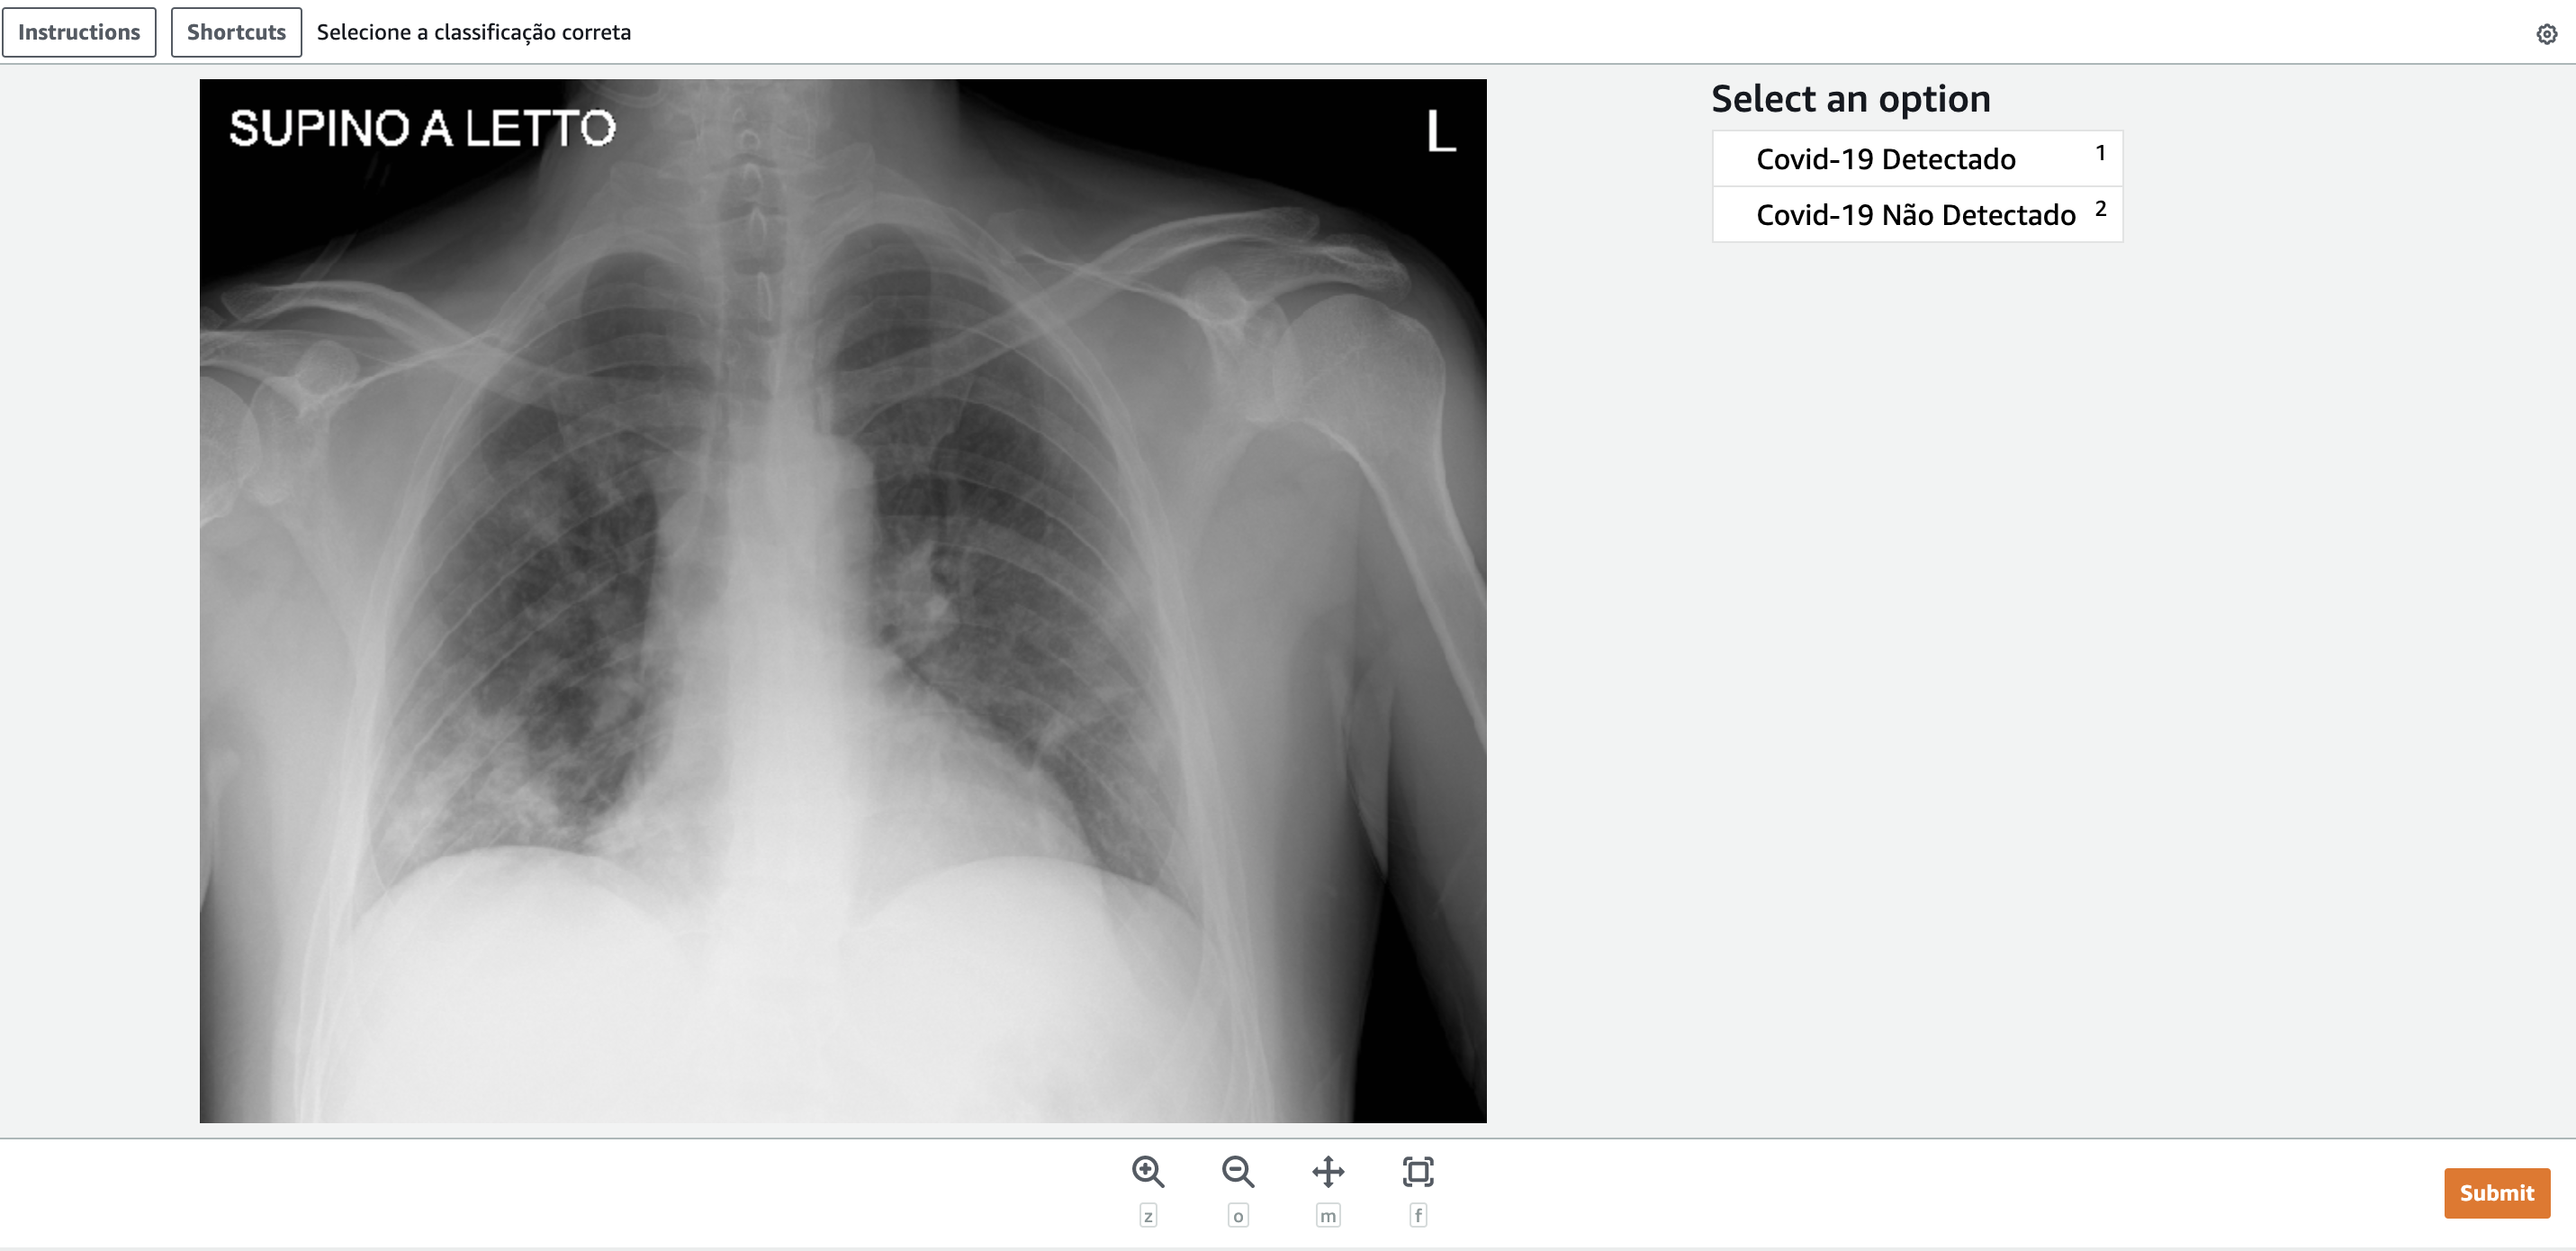

Ao selecionarmos a tarefa e clicarmos em Start working, teremos a tela abaixo:

No caso acima, a imagem pertencia a classe “Detectado”. Selecionamos a opção correta (1) e clicamos em “Submit”. A tarefa vai ser finalizada e o resultado vai ser armazenado do s3 informado no momento da criação do flow.

Interessante observar que a tela foi formada com base no nosso template e é amplamente customizável para conter outras categorias, textos, descrições e afins. No link citado anteriormente temos outras sugestões de templates para criarmos a interface da nossa tarefa.